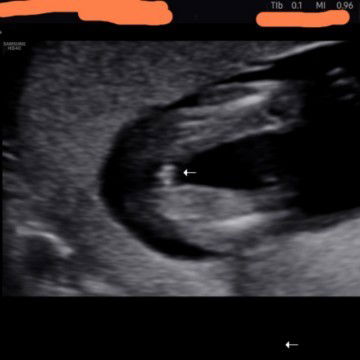

Hi mommies out there.. rasa² yg ni nampak mcm boy or girl ye.. doc x bole nk confirmkn lg..

Mcm boy , nak lebih tepat scan balik waktu 22 minggu